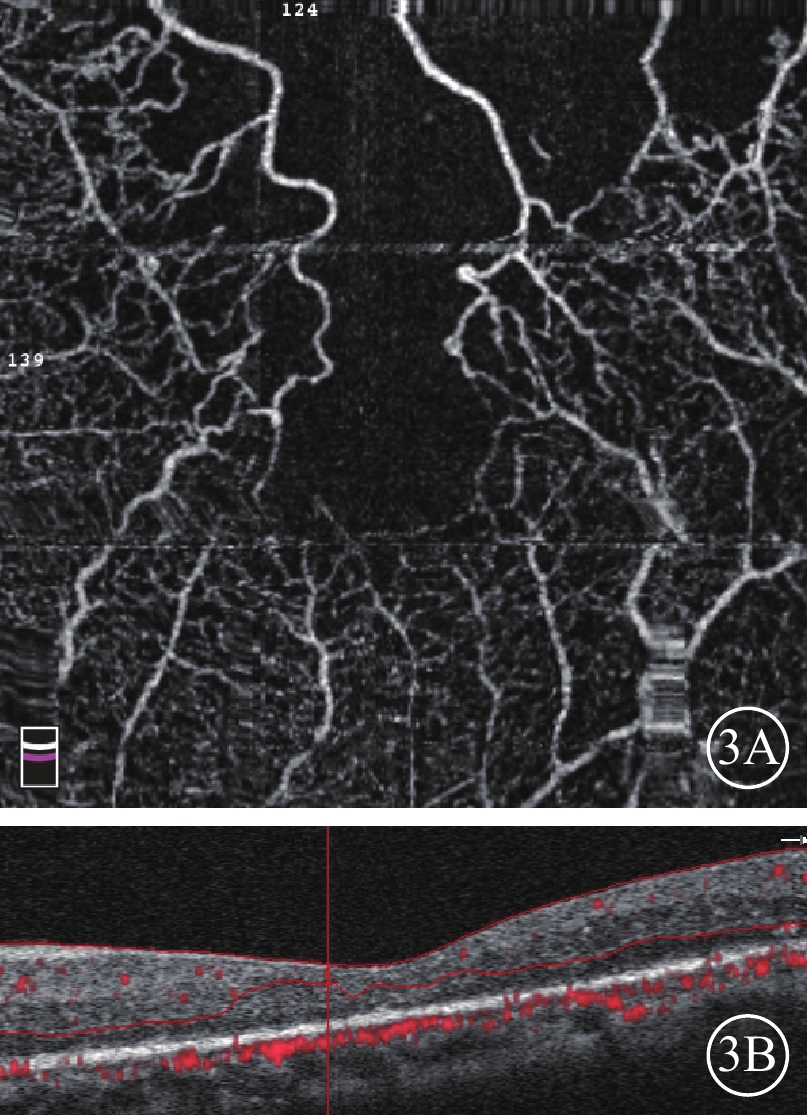

圖3

BRVO患眼OCTA像及B-scan像。3A示OCTA像,FAZ面積明顯擴大,上方大片無血流區;3B示B-scan像,視網膜無水腫,厚度變薄

圖3

BRVO患眼OCTA像及B-scan像。3A示OCTA像,FAZ面積明顯擴大,上方大片無血流區;3B示B-scan像,視網膜無水腫,厚度變薄

依據黃斑水腫程度將72例75只眼分為M300組(CRT≥300 μm)、L300組(CRT<300 μm),分別為38例39只眼和34例36只眼。M300組38例中,男性27例,女性11例;平均年齡(59.31±9.09)歲;平均CRT(474.00±157.03)μm。39只眼中,Major型、Macular型分別為28、11只眼。FAZ破壞27只眼。黃斑水腫已消退3只眼;黃斑中心凹變薄呈萎縮、缺血狀態1只眼;黃斑囊樣水腫14只眼,彌漫性水腫2只眼,視網膜下液型水腫3只眼;混合型水腫19只眼,其中存在視網膜下液14只眼。L300組34例中,男性13例,女性21例;平均年齡(52.44±9.75)歲。平均CRT(244.33±34.55)μm‘。36只眼中,Major型、Macular型分別為24、11只眼。FAZ破壞23只眼。黃斑水腫已消退14只眼;黃斑中心凹變薄呈萎縮、缺血狀態(圖3)7只眼;黃斑囊樣水腫9只眼,彌漫性水腫2只眼,混合型水腫2只眼。

圖3

BRVO患眼OCTA像及B-scan像。3A示OCTA像,FAZ面積明顯擴大,上方大片無血流區;3B示B-scan像,視網膜無水腫,厚度變薄

圖3

BRVO患眼OCTA像及B-scan像。3A示OCTA像,FAZ面積明顯擴大,上方大片無血流區;3B示B-scan像,視網膜無水腫,厚度變薄